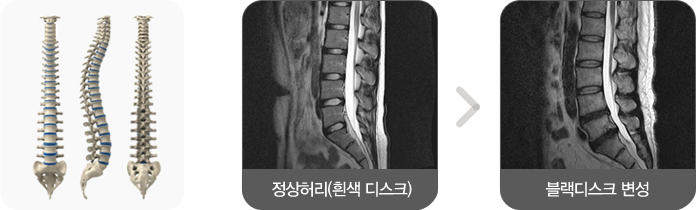

디스크가 탈출되어 신경을 누르는 허리디스크 질환과 달리 디스크는 튀어 나오지 않았지만 퇴행성으로 변성된 디스크에 의해 허리통증이 생기는 경우를 디스크 내장증이라고 합니다.

원래 디스크는 척추뼈와 뼈 사이에 있는 물렁뼈 조직으로 젤리나 인절미와 같이 탄력있고 수분이 풍부한 상태입니다.

하지만, 이러한 디스크가 반복적으로 외부의 충격을 받게 되면 수분 성분이 줄고 MRI 검사에서 봤을 때 검은색으로 보이는 블랙디스크(Black disc) 변성을 일으키게 되고, 이렇게 디스크 내부에 변성이 일어나게 되면 손상된 부분에서 염증물질이 나오면서 허리 통증을 유발하게 되는 상태입니다.